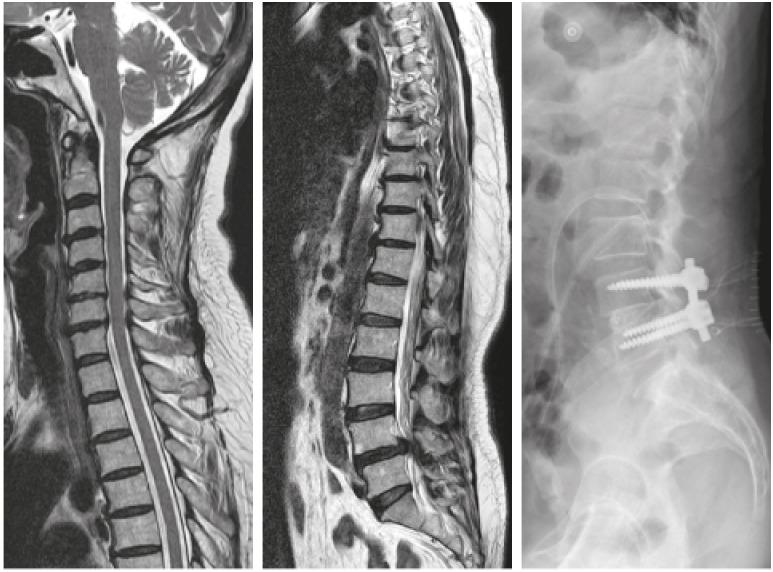

全脊柱 T2 矢状位 MRI 评估脊柱退行性疾病中的并存脊柱病变。

Coexisting Spine Lesions on Whole Spine T2 Sagittal MRI in Evaluating Spinal Degenerative Disease.

Studies have reported on the usefulness of whole spine magnetic resonance imaging (MRI) in evaluating specific diseases such as spinal tuberculosis, spinal trauma, spondyloarthropathies, and multiple myeloma. In studies concerning degenerative spinal disease, sample sizes were small and some did not provide information on how symptomatic coexisting lesions were treated. We evaluated the types and prevalence of coexisting spine lesions found on whole spine T2 sagittal screening performed at the time of routine cervical and lumbar spine MRI and evaluated the efficacy of such screening in degenerative diseases of the cervical and lumbar spine.

研究报告了全脊柱磁共振成像(MRI)在评估特定疾病方面的有用性,如脊柱结核、脊柱创伤、脊柱关节病和多发性骨髓瘤。在涉及退行性脊柱疾病的研究中,样本量较小,并且有些研究没有提供关于如何治疗同时存在的症状性病变的信息。我们评估了在常规颈椎和腰椎 MRI 时进行全脊柱 T2 矢状位筛查时发现的共存脊柱病变的类型和患病率,并评估了这种筛查在颈椎和腰椎退行性疾病中的效果。